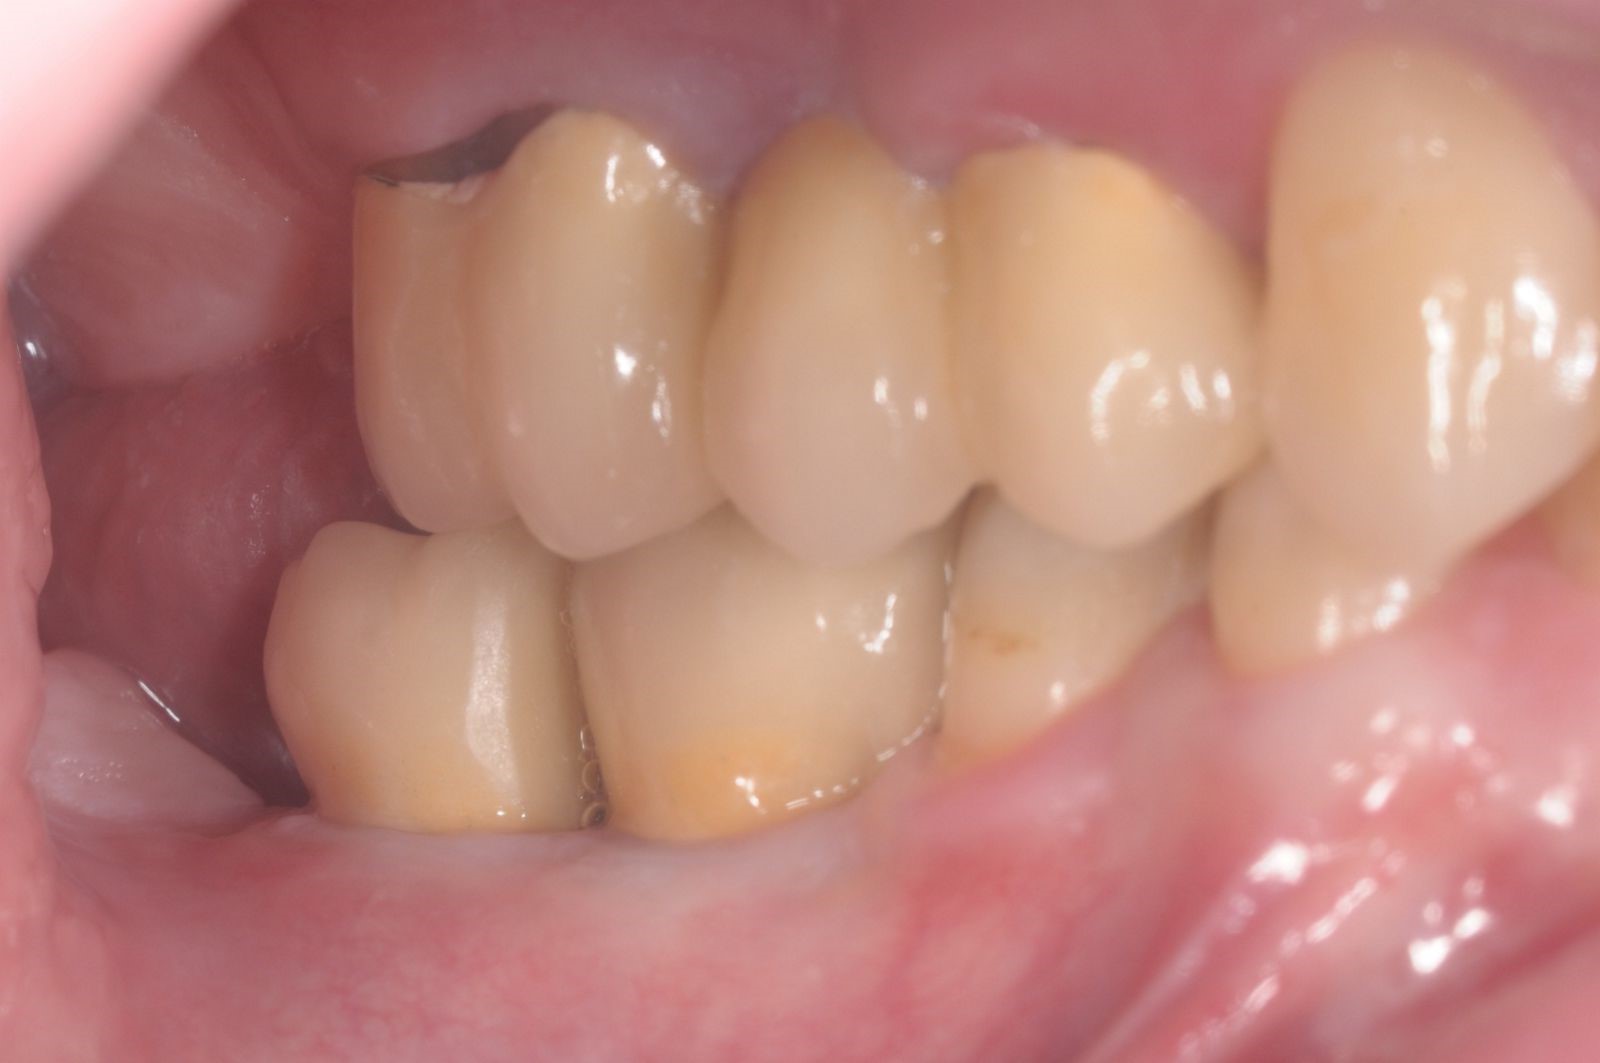

27/28 - Aesthetic and functional final resultThree-dimensional augmentation with maxgraft® cortico - Dr. R. Würdinger